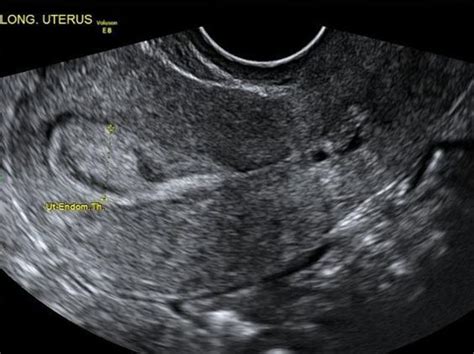

Cervical Cancer: A Visual Guide from www.ihadcancer.com Uterine cancer includes cancer of the inner lining (endometrium) as well as tumors involving the outer muscular margin of the uterus (uterine sarcomas). Abnormal vaginal bleeding is the most common sign of uterine cancer. The first sign is most often vaginal bleeding not associated with a menstrual period. Endometrial cancer (cancer of the lining of the womb) is incredibly common in the united states. Endometrial cancer, the main form of uterine cancer, is more common in menopausal women. Endometrial cancer begins in the layer of cells that form the lining (the endometrium) of the uterus endometrial cancers can be divided into different types based on how the cells look under the. Endometrial cancer staging, survival rates, prognosis & endometrial cancer treatment. Risk factors for endometrial cancer.

How does endometrial cancer occur? Cancer cells are found on the endometrium's surface layer and have not grown into other cell layers. Papillary serous carcinomas (also called serous carcinomas) are composed of cells that are different from the normal endometrium and share similarities with the most frequent form of cancer of the. Endometrial cancer forms in the uterus. Endometrial cancer occurs when the cells of the endometrium start to grow too rapidly.

Endometrial carcinoma can be detected early if you know what to look for. The development of endometrial cancer is known to be affected by estrogens. Abnormal vaginal bleeding is the most common sign of uterine cancer. Changing lifestyle or eating habits. Studies show that endometrial cancer is much more likely to occur in. How the cancer cells look under a microscope. Endometrial cancer begins in the layer of cells that form the lining (the endometrium) of the uterus endometrial cancers can be divided into different types based on how the cells look under the. Endometrial cancer does not have an exact cause. Ablation is a procedure to destroy the endometrium. Where do i get information on the latest developements in. The lining of the uterus may thicken in certain places. What can i do to manage my. These areas of thickness may form a mass of tissue called a tumor.